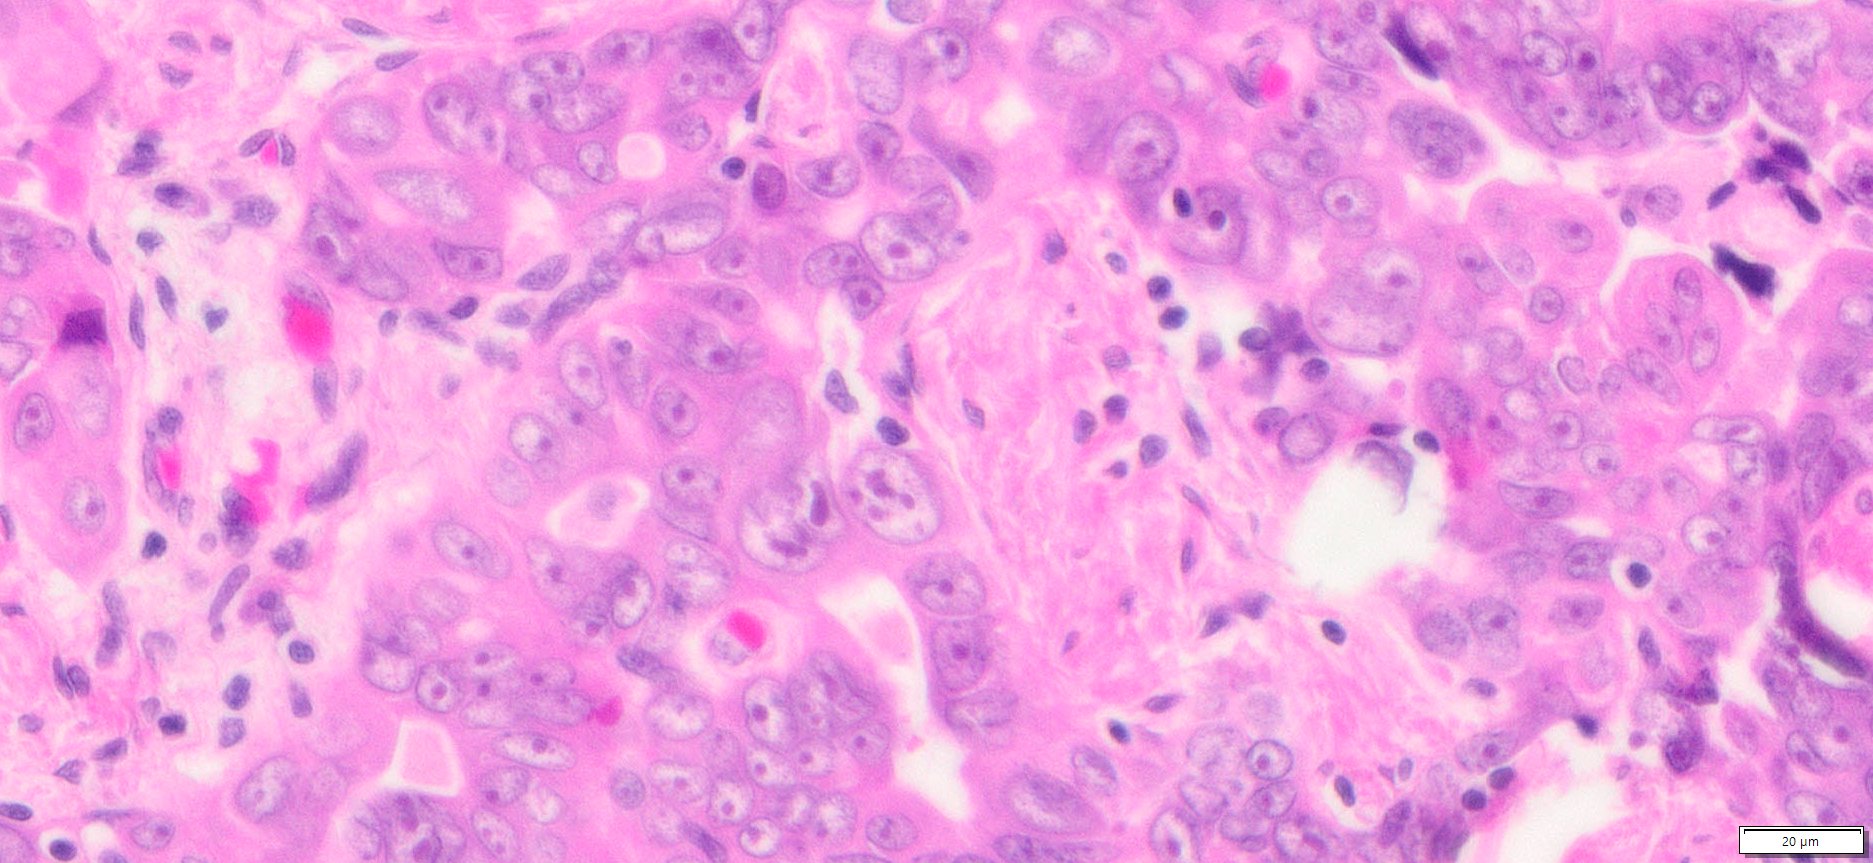

Description

| Organ& Tissue | Pathology Diagnosis | Gender/Age | % Tumor Area | Grade | TMN Stage | IHC Biomarkers |

| Human Ovary | High Grade Serous Carcinoma (HGSC) FFPE Sections | Female/61 | 30% | III | pT3cpNxMx | NA |

More Images of H&E Stain and IHC